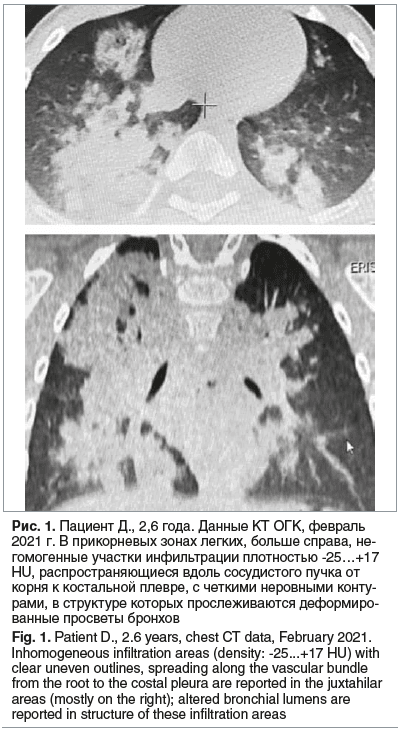

При осмотре: состояние средней тяжести по основному заболеванию. Самочувствие удовлетворительное. Температура тела 37,1 °С. Катаральных явлений нет. Кожные покровы бледно-розовые, чистые. Отмечалось умеренное тахипное, одышка при беспокойстве и плаче. Над легкими перкуторный звук не изменен. Аускультативно в легких дыхание справа ослаблено, слева пуэрильное, хрипов нет. Сатурация 98%. Частота сердечных сокращений 108 в 1 мин. Тоны сердца ясные, ритмичные. При беседе с матерью установлено, что ребенок на протяжении 6 мес. продолжает получать перорально вазелиновое масло, при этом периодически отмечались эпизоды поперхивания, которые сопровождались редким кашлем и купировались при смене ребенком положения тела (из горизонтального в сидячее). На КТ ОГК в феврале 2021 г. выявленные изменения с учетом анамнеза трактовались как признаки двусторонней ЛП (рис. 1).

Компьютерная томография ОГК является «золотым стандартом» в диагностике этого заболевания. При интерпретации результатов исследования следует учитывать патогномоничные признаки: участки снижения пневматизации по типу «матового стекла», окруженные зонами консолидации, а также неоднородные участки уплотнения легочной ткани с показателями плотности в диапазоне от -30 до -150 HU, что характерно для интерстициального накопления жира [26, 27, 34].